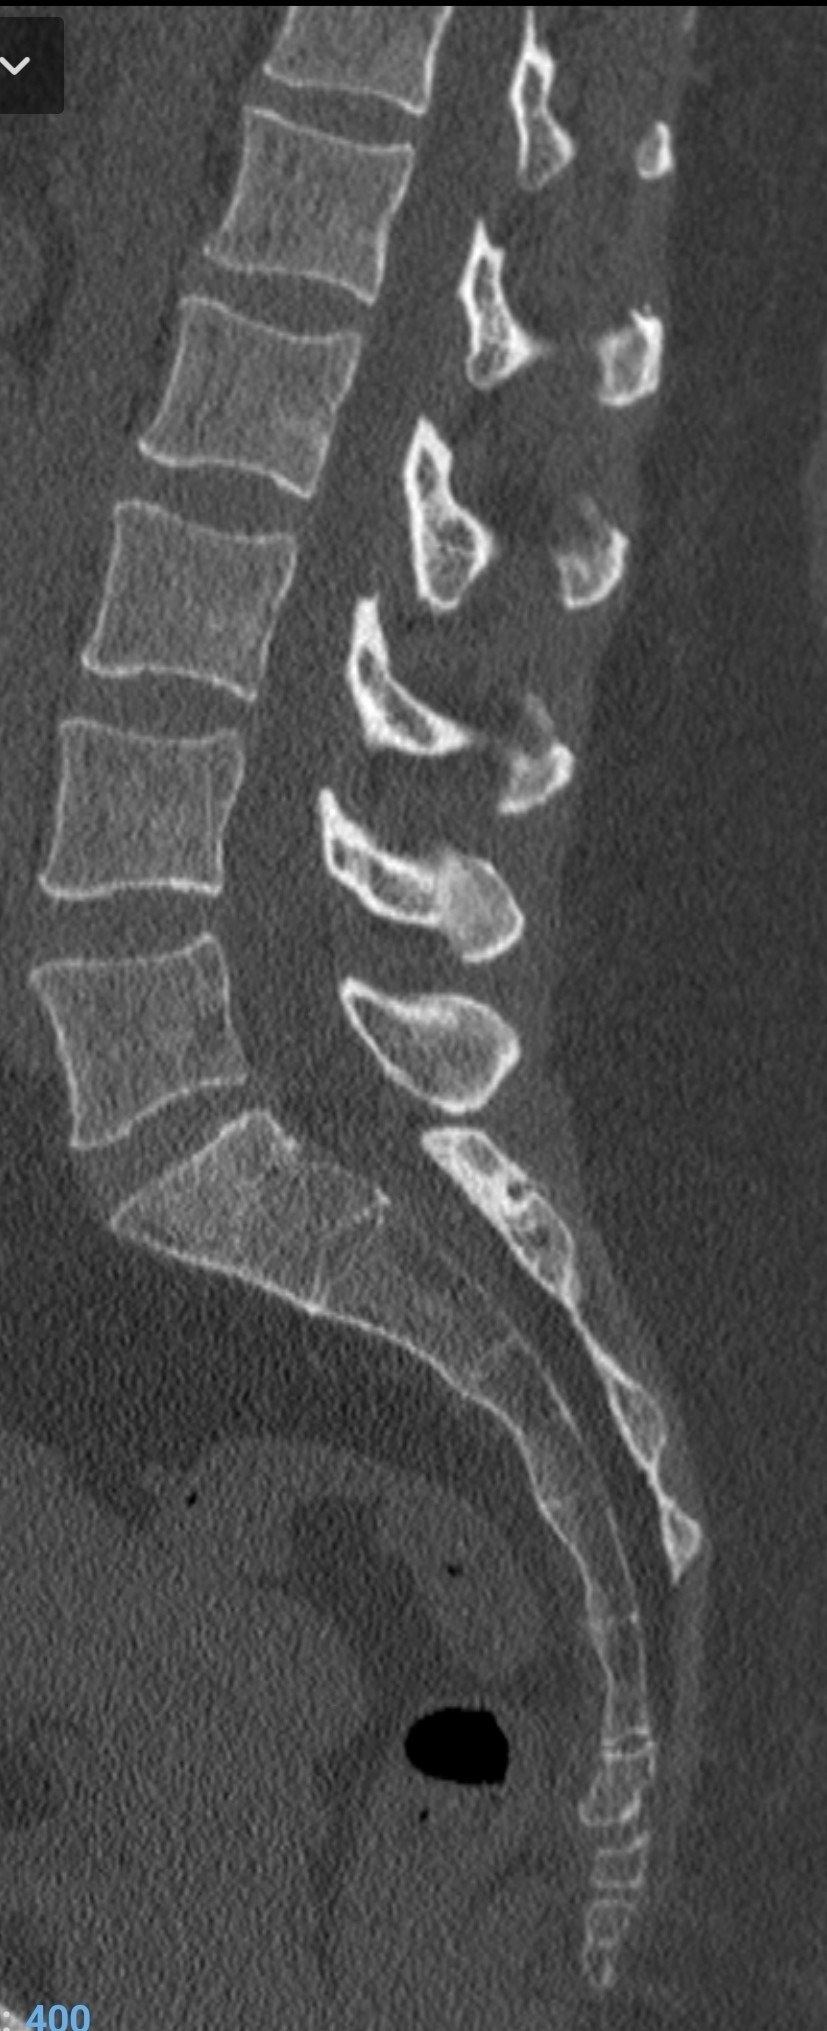

Здравствуйте, подскажите, пожалуйста. Неделю назад подскользнулась на лестнице и получила травму в районе копчика. Сделали КТ, жду результат. Проконсультируйте, почему болит? Есть ли ушиб или вывих? Болит при наклоне, вставании, при напряжении в районе ануса, при лежании на спине. Когда хожу чувствую распирание и напряжение в районе копчика, но не болит. Заранее благодарю.